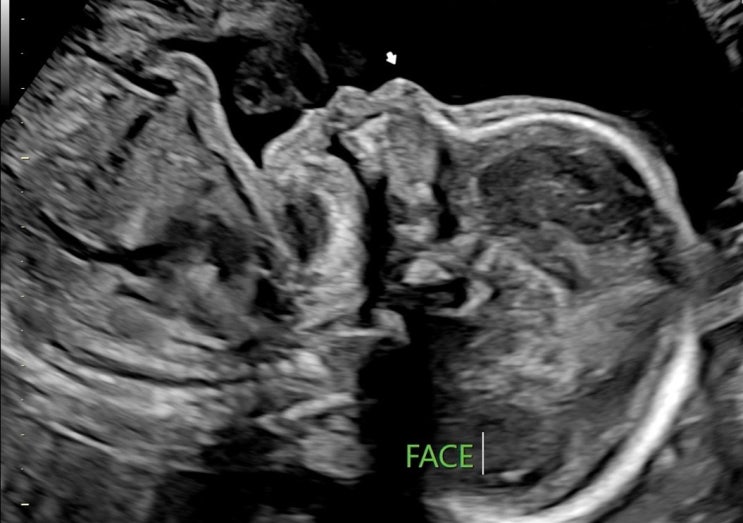

임신 26주 :: 산본제일병원 입체초음파 후기, 5D 정밀초음파 시기

임신 26주 2일차 26w2d 9월 28일 이전 이야기 : 임당 재검사 후기 원래대로라면 오늘 “임당 검사 + 입체 ...